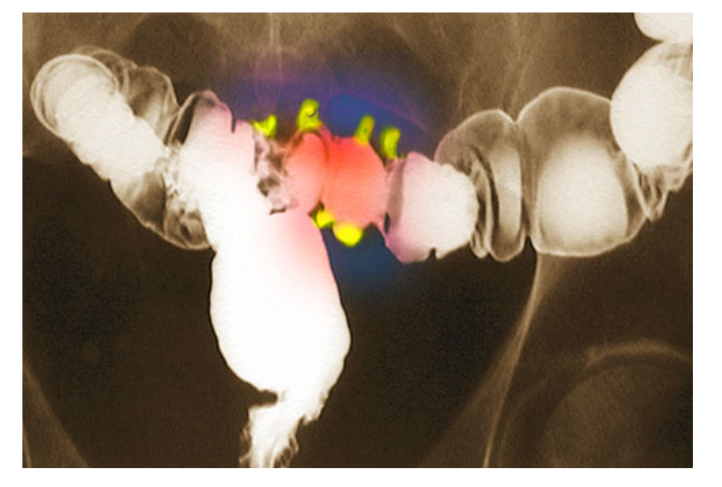

Mọi người có thể phát triển các túi nhỏ phồng lên trong niêm mạc ruột già. Khi các túi bị viêm hoặc nhiễm trùng, nó dẫn đến tình trạng rất...